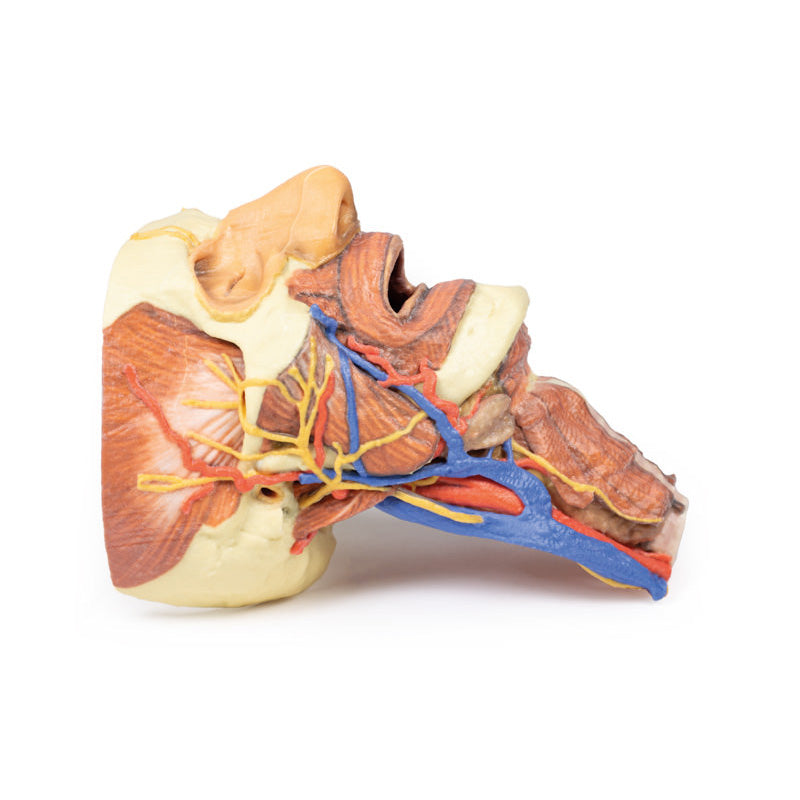

The face: On the right side of the head the parotid gland has been removed to reveal the facial nerve and all its branches (temporal, zygomatic, buccal, marginal mandibular and cervical) and demonstrate the spatial relations of structures embedded in the gland from superficial to deep (facial nerve, retromandibular vein, external carotid artery). In the surrounding region the temporalis, masseter and posterior belly of digastric are exposed, as are and the facial artery, transverse facial artery and superficial temporal artery. The facial vein and transverse facial vein are clearly visible uniting to form the common facial vein which is joined by the retromandibular vein to form the external jugular vein.

Viewed from the anterior aspect the face has been dissected to display some of the facial muscles around the mouth (buccinator [on the left], orbicularis oris and zygomaticus major). On the left side of the infratemporal fossa has been open to expose the medial and lateral pterygoids.

The lateral pterygoid is divided to show the mandibular division of the trigeminal nerve dividing into the lingual nerve and the inferior alveolar branch. Also on the left side the branches of the ophthalmic division of the trigeminal that supply the skin above the eyebrows and scalp (supraorbital [left only] and supratrochlear nerves [both sides]) are dissected. The submandibular gland is clearly visible below the mandible on both sides as are the facial arteries and veins as they course over the mandible.

The neck: The musculoskeletal portion of the neck have been removed to display the pharynx posteriorly, the larynx anteriorly, and the neurovascular bundles laterally. The suprahyoid and infrahyoid muscles can be seen on the neck, as well as the cricothyroid muscle.

When looking up the length of the trachea from below, the vocal folds are visible. The hypoglossal nerve can be seen winding around the lateral surface of the external carotid artery and the external branch of superior laryngeal nerve is seen descending in the neck. The internal jugular vein, the common carotid artery and its bifurcation into external and internal carotid arteries are clearly seen on both left and right. The vagus nerve in the carotid sheath is also visible. The ansa cervicalis is visible emerging below the digastric muscle and descending on the surface of the internal jugular vein. The internal branch of the superior laryngeal nerve can be seen below the superior thyroid artery on the left. The superior thyroid artery branching from the external carotid artery is seen descending in the anterior neck. The internal branch of the superior laryngeal artery is visible on the left piercing the thyrohyoid membrane above the inferior constrictor where this muscle is attached to the hyoid bone.

Posterior view of the pharynx: The superior, middle and inferior pharyngeal constrictors are indicated on the pharynx wall. The oesophagus can be identified emerging from the lower end of the pharynx. The posterior horn of the hyoid bone acts as a useful landmark. The carotid sheath seen from behind clearly shows the vagus nerve and its pharyngeal branches on the left. The recurrent laryngeal nerve is briefly visible on the left lying medial to the inferior thyroid artery. The occipital arteries are visible as they curve around the mastoid process. The vertebral arteries are seen either side of the brainstem as they enter the foramen magnum. The cerebellum has been removed to allow the fourth ventricle to be exposed. The cut surfaces of the cerebellar peduncles are clearly visible. A large portion of the posterior inferior cerebellar artery on the right is still visible as it winds around around the brainstem.

This 3D print specimen preserves a series of features of the head and visceral column of the neck:The face: On the right side of the head the parotid gland has been removed to reveal the facial nerve and all its branches (temporal, zygomatic, buccal, marginal mandibular and cervical) and demonstrate the spatial relations of structures embedded in the gland from superficial to deep (facial nerve, retromandibular vein, external carotid artery). In the surrounding region the temporalis, masseter and posterior belly of digastric are exposed, as are and the facial artery, transverse facial artery and superficial temporal artery. The facial vein and transverse facial vein are clearly visible uniting to form the common facial vein which is joined by the retromandibular vein to form the external jugular vein.

Viewed from the anterior aspect the face has been dissected to display some of the facial muscles around the mouth (buccinator [on the left], orbicularis oris and zygomaticus major). On the left side of the infratemporal fossa has been open to expose the medial and lateral pterygoids.

The lateral pterygoid is divided to show the mandibular division of the trigeminal nerve dividing into the lingual nerve and the inferior alveolar branch. Also on the left side the branches of the ophthalmic division of the trigeminal that supply the skin above the eyebrows and scalp (supraorbital [left only] and supratrochlear nerves [both sides]) are dissected. The submandibular gland is clearly visible below the mandible on both sides as are the facial arteries and veins as they course over the mandible.

The neck: The musculoskeletal portion of the neck have been removed to display the pharynx posteriorly, the larynx anteriorly, and the neurovascular bundles laterally. The suprahyoid and infrahyoid muscles can be seen on the neck, as well as the cricothyroid muscle.

When looking up the length of the trachea from below, the vocal folds are visible. The hypoglossal nerve can be seen winding around the lateral surface of the external carotid artery and the external branch of superior laryngeal nerve is seen descending in the neck. The internal jugular vein, the common carotid artery and its bifurcation into external and internal carotid arteries are clearly seen on both left and right. The vagus nerve in the carotid sheath is also visible. The ansa cervicalis is visible emerging below the digastric muscle and descending on the surface of the internal jugular vein. The internal branch of the superior laryngeal nerve can be seen below the superior thyroid artery on the left. The superior thyroid artery branching from the external carotid artery is seen descending in the anterior neck. The internal branch of the superior laryngeal artery is visible on the left piercing the thyrohyoid membrane above the inferior constrictor where this muscle is attached to the hyoid bone.

Posterior view of the pharynx: The superior, middle and inferior pharyngeal constrictors are indicated on the pharynx wall. The oesophagus can be identified emerging from the lower end of the pharynx. The posterior horn of the hyoid bone acts as a useful landmark. The carotid sheath seen from behind clearly shows the vagus nerve and its pharyngeal branches on the left. The recurrent laryngeal nerve is briefly visible on the left lying medial to the inferior thyroid artery. The occipital arteries are visible as they curve around the mastoid process. The vertebral arteries are seen either side of the brainstem as they enter the foramen magnum. The cerebellum has been removed to allow the fourth ventricle to be exposed. The cut surfaces of the cerebellar peduncles are clearly visible. A large portion of the posterior inferior cerebellar artery on the right is still visible as it winds around around the brainstem.